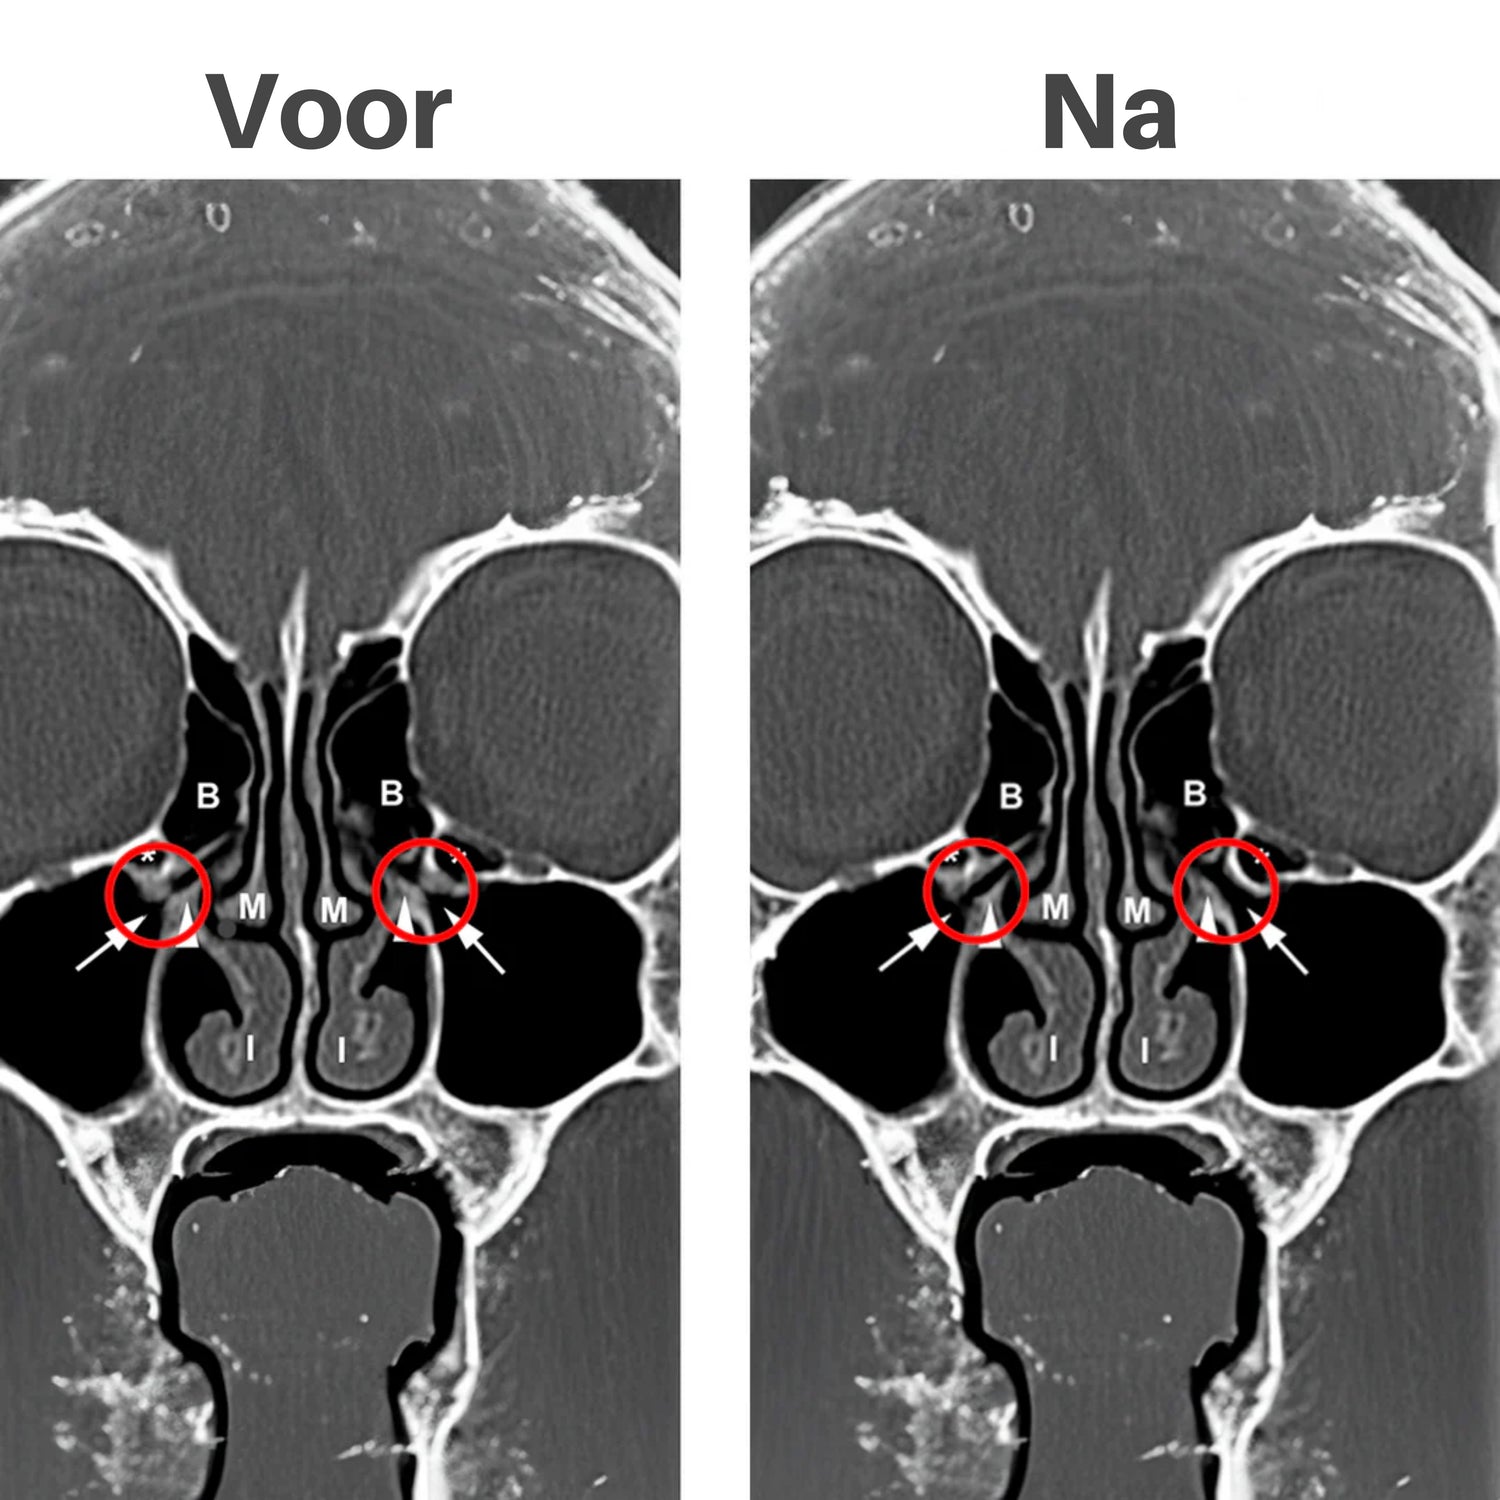

Het is een draagbaar, gericht roodlichtapparaat dat met 660 nm frequentie diep in je neusholtes doordringt. Het verlicht zwelling, breekt slijm af en kalmeert ontstoken weefsel. Hierdoor voel je je luchtwegbelemmering afnemen, kun je vrijer ademhalen en ervaar je een frisse, lichte sinus, zonder medicijnen of pillen. Een echte doorbraak in sinuscomfort

Het rode licht van 660 nm dringt direct door tot in de neusholtes, waar het zwelling en irritatie aanpakt bij de bron. In plaats van oppervlakkige verlichting, krijg je echte, voelbare ontspanning van binnenuit.

Kalmeert druk en ontspant gezichtsweefsel

Door gerichte roodlichttherapie neemt de zwelling af en wordt de doorbloeding hersteld. Je voelt niet alleen verlichting, maar juist die zachte warmte, alsof iemand je gezicht streelt en alle spanning wegvaagt. Eindelijk adem je vrij, gewoon door je neus.

Helpt slijm afvoeren voor een frisse neus

Het licht helpt het slijmvlies te herstellen, vocht losser te maken en slijm af te voeren. Voel je weer fris en licht, alsof je sinus opnieuw ademt. Geen gedoe meer met tissues of congestie, maar helderheid die opstaat met je mee de dag begint.